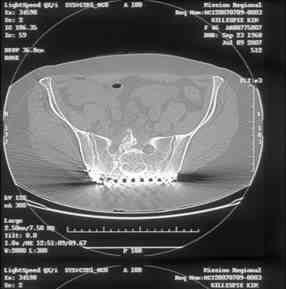

[Ortho] Sacral Non-Union

----------- следущая часть -----------

Вложение не в текстовом формате было извлечено…

Имя     : slide0002_image004.jpg